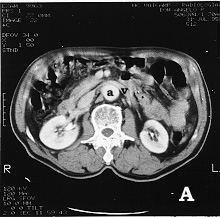

Figura 1: Tomografia computadorizada de abdome com contraste. A - imagem da aorta (a) na altura da veia renal E (v), revelando um calibre normal abaixo das artérias renais. B - imagem do maior diâmetro do aneurisma (a), com ausência de trombo mural, e C - imagem do aneurisma de ilíaca D (a1) com presença de trombo mural (t) e ilíaca E com diâmetro pouco aumentado (a2). |